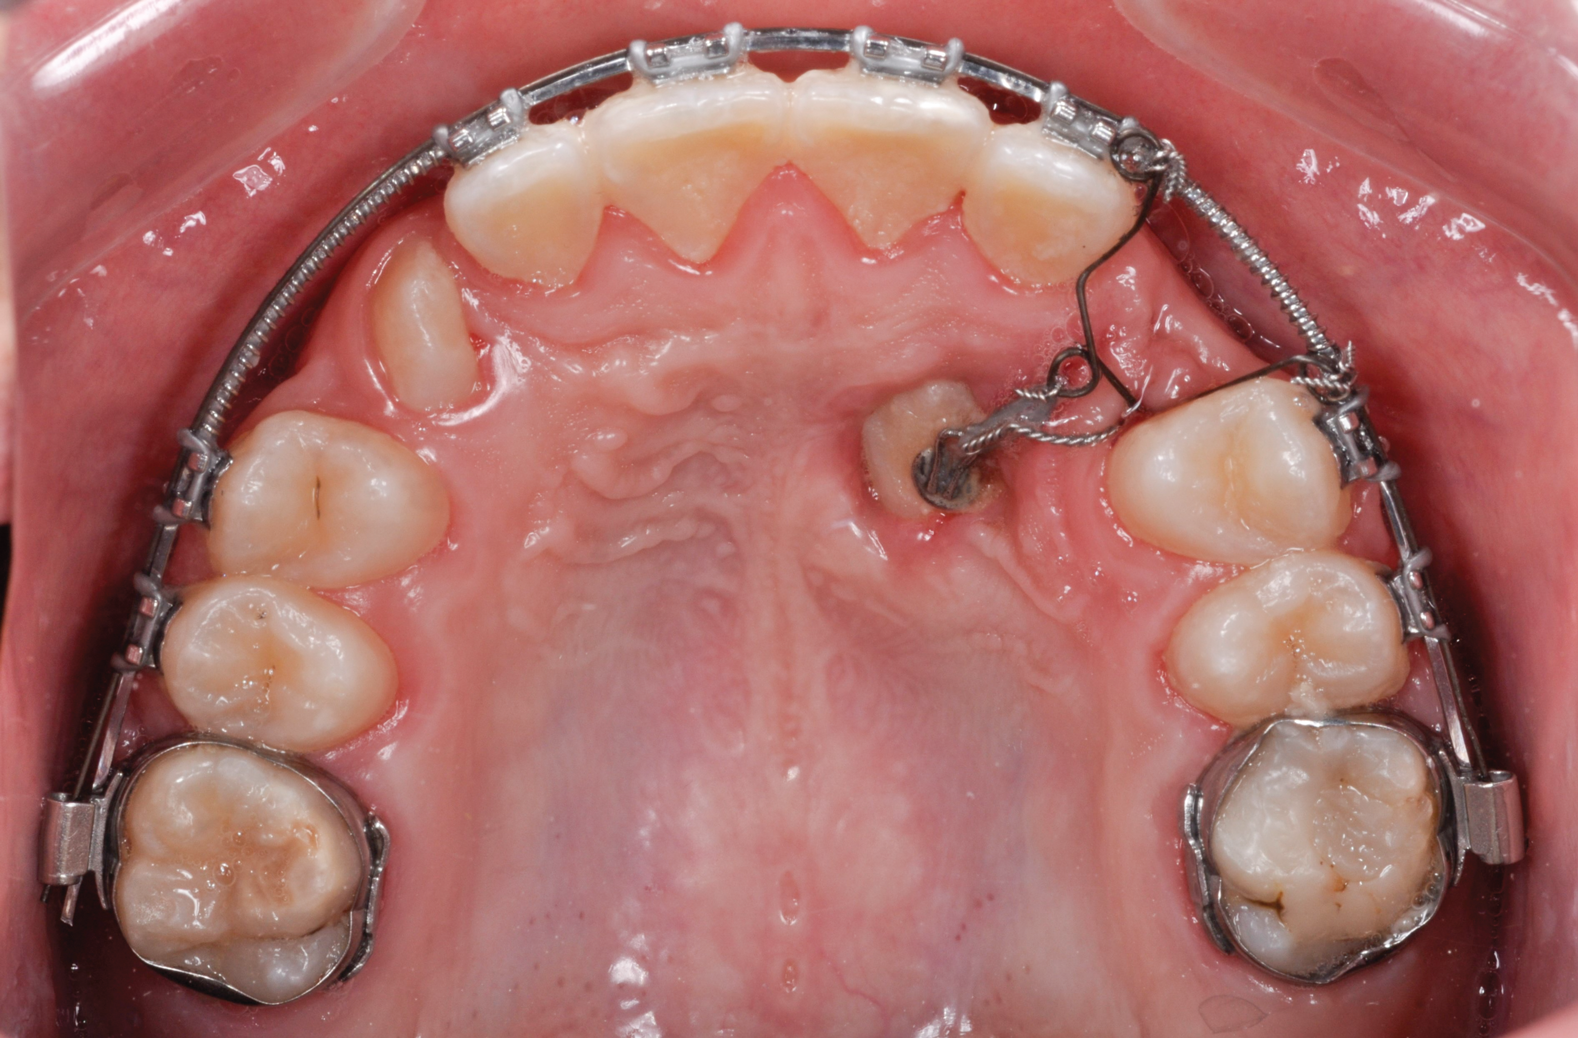

Various external elements, such as swinging gates, transpalatal arches, Hass expanders, quad helixes, Hyrax expanders, and temporary anchorage devices (TADs), have been used as alternative anchorage apparatuses. In the case of a transpalatal bar, the objective is to use cantilever extension arms to traction the impacted canine into the palate. This is followed by traction of the canine into its final position using positioning springs or other methods to bring the impacted tooth into the dental arch (Figure 4 and Figure 5).

Fig 4. Swinging gate type of auxiliary used for direct traction of a palatal canine managed with open exposure.

Figure 4

Fig 5. Open exposure of a palatal impacted canine. A transpalatal bar was used as an anchorage source with an extension arm designed for direct traction.

Figure 5

Fig 8. Open exposure (Fig 8) with spontaneous eruption for 7 months. Once the canines reached the occlusal plane, buccal traction was performed for an additional 5 months. Total treatment time to move the bilateral palatal impacted canines into the arch was 12 months (Fig 9).

Figure 8

Fig 9. Open exposure (Fig 8) with spontaneous eruption for 7 months. Once the canines reached the occlusal plane, buccal traction was performed for an additional 5 months. Total treatment time to move the bilateral palatal impacted canines into the arch was 12 months (Fig 9).

Figure 9